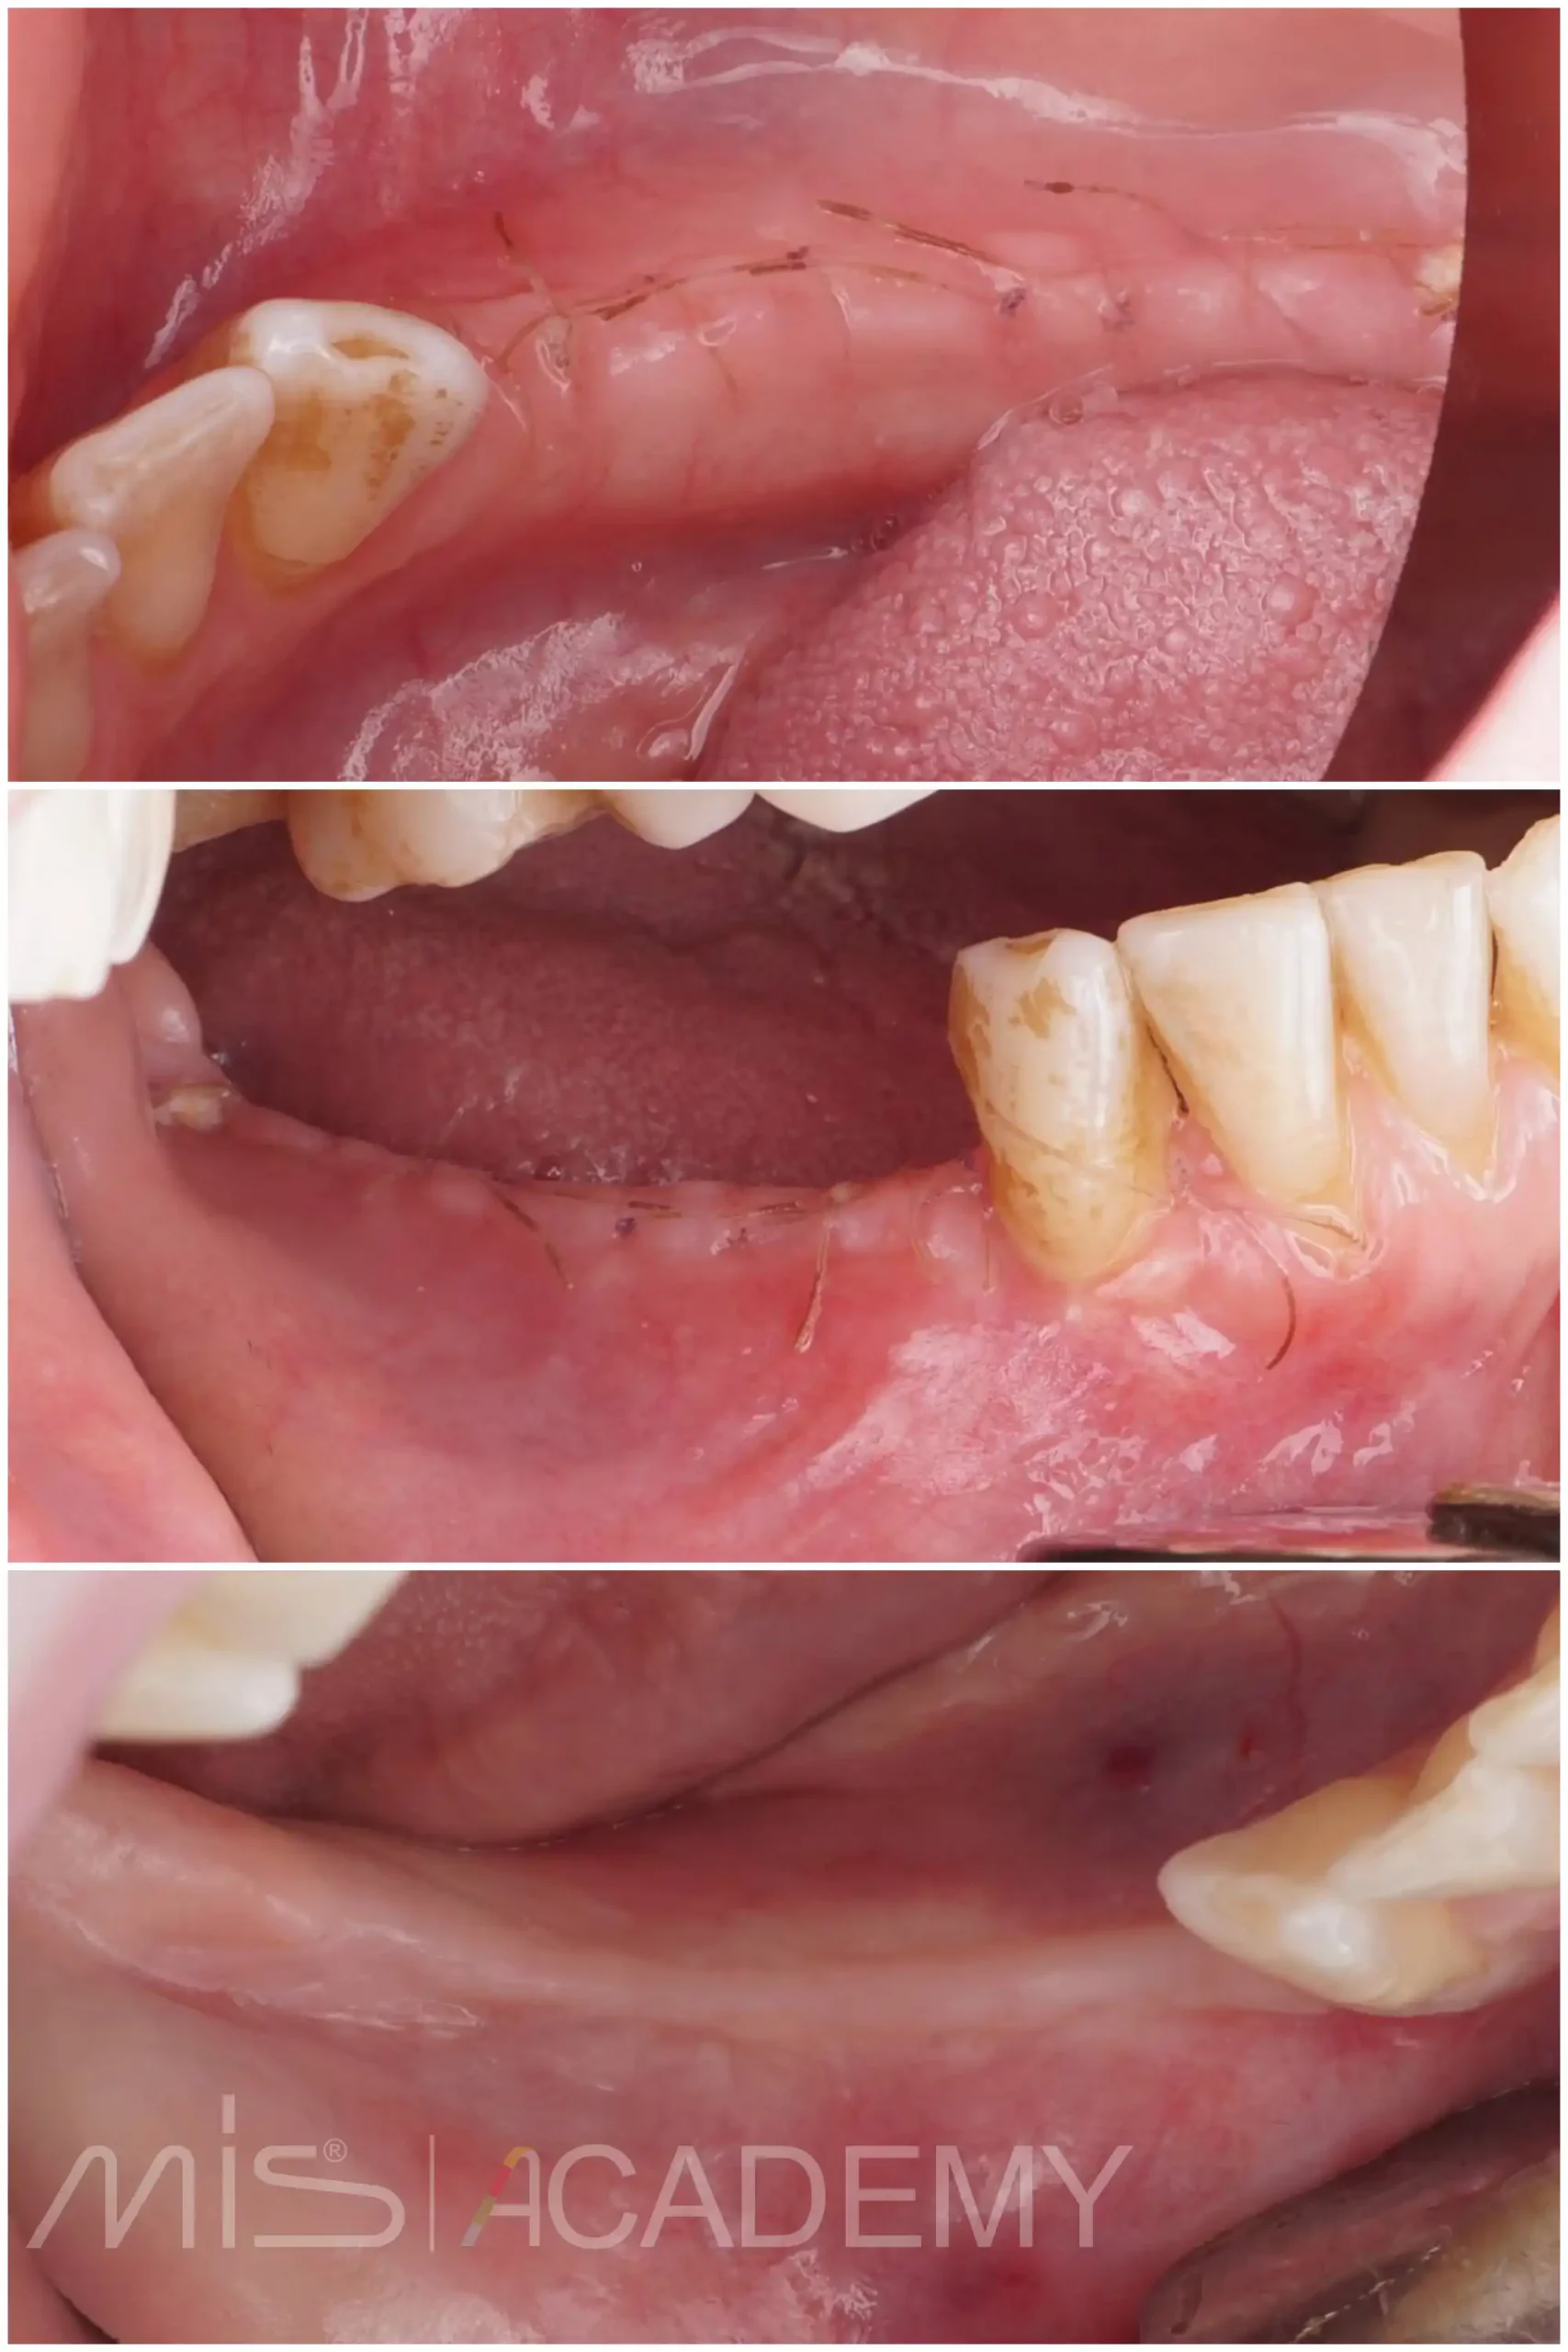

— Снятие швов через 2 недели.

Продолжение следует …